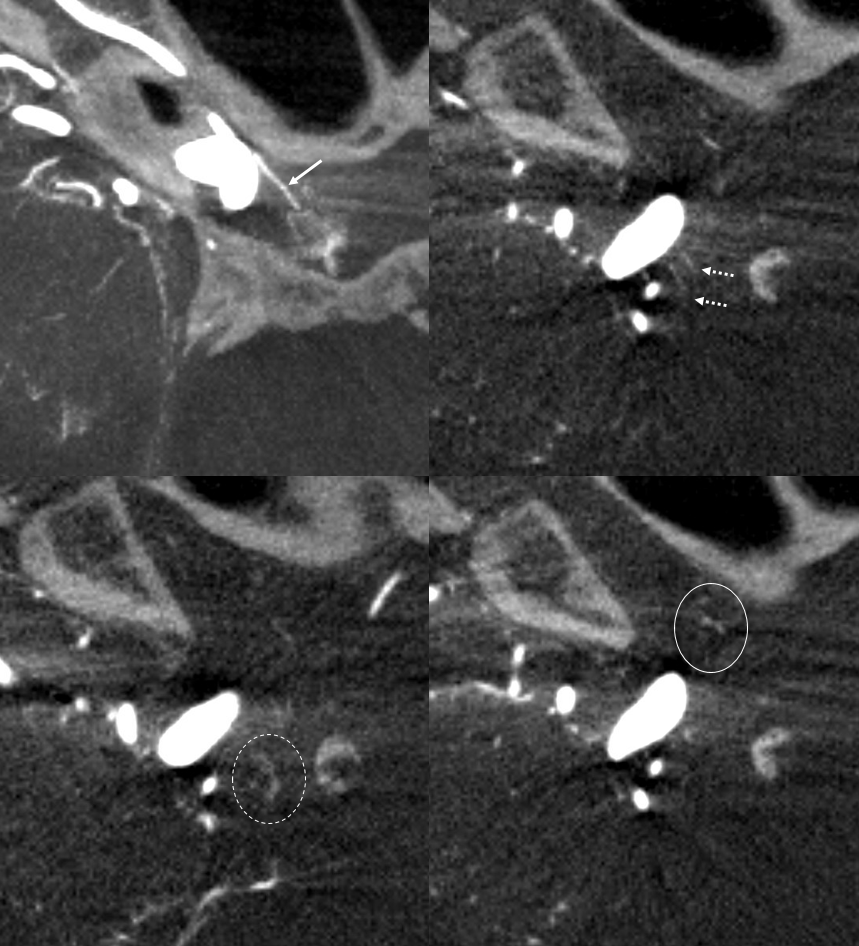

Optic Nerve Supply

What supplies the bulk of optic nerve? Central Retinal artery is for the distal portion of nerve and retina. What about the rest — intracranial, intracanalicular, proximal intraconal segments? The answer is not clear (let me know if you do), but i believe the bulk of it comes from the superior hypophyseals. It is probably in balance with the recurrent branch of the central retinal artery. Below is an example of an especially prominent proximal-most superior hypophyseal (arrows) supplying the pituitary stalks and optic nerve in the canalicular and intracranial locations. Note how well one can see the branch in coronal view (bottom left image). In this case there are two large superior hypophyseals — the more distal one (dashed arrows) supplies predominantly the pituitary stalk. The inferior hypophyseal artery is marked by arrowhead. Lower right image is coronal.

Movie is the best way

Here too superior hypophyseal (arrow) supply of the intracranial optic nerve (oval) and possibly chiasm is shown definitively (lower right image is coronal)